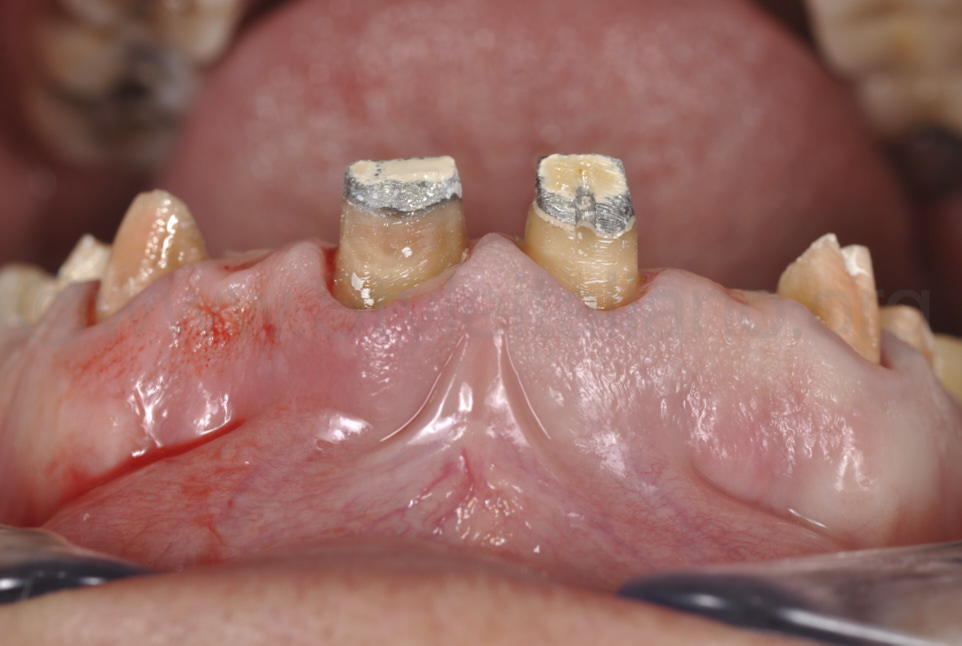

Фото 5.

Видалено старі реставрації, та виконано повторне препарування зубів і контурування ясен.